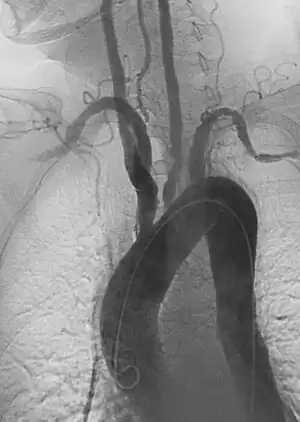

Aneurysm refers to pathologic dilation of an artery to greater than 1.5 times its normal size. True vascular aneurysms are due to degenerative processes in the wall of the artery. Aneurysms can be solitary or multiple and are sometimes found in association with various clinical syndromes, including forms of vasculitis or connective tissue diseases. Aneurysms are typically classified by major shapes, either fusiform (tubular) or saccular (eccentric). Ectasia is another broad term for an enlarged vessel, but is not necessarily pathological. Rupture is a dreaded complication of aneurysms that can lead to extensive, difficult to control bleeding. Aneurysms can also clot, or thrombose, and rapidly occlude the involved vessel, leading to acute distal ischemia.

Aortic aneurysms include thoracic, abdominal and thoracoabdominal aneurysms. Treatment strategies are customized depending on the location, size, rate of growth and extent of the aneurysm as well as the medical comorbidities of the patient. For example, an intact, small but slowly growing aneurysm may be safely monitored with serial imaging for months or years before elective repair is considered. Elective endovascular aortic grafting is now routinely attempted when possible. Endovascular aortic repair (EVAR) refers to treatment of an abdominal aortic aneurysm, while thoracic endovascular aortic repair (TEVAR) is performed on the thoracic aorta. A ruptured aneurysm may be taken emergently for open, endovascular or combination repair.

A variety of endovascular grafts are available, and each has advantages and disadvantages depending on the characteristics of the aneurysm and patient.[90]